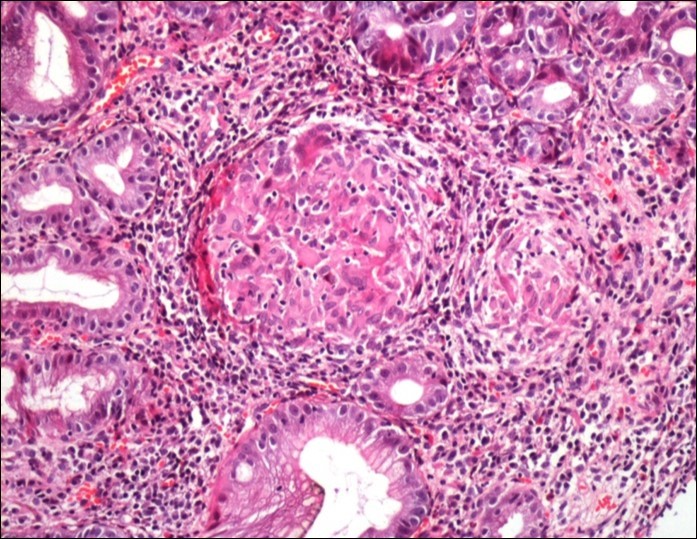

Concerning the etiology, diagnosis was made regarding to the past medical facts, the clinical symptoms, the endoscopic findings and the histological associated lesions. The main etiology was represented by Crohn’s disease in ten cases, followed by gastric tuberculosis in 6 cases. H Pylori was the retained cause of gastric granulomatosis in 5 cases, regarding to the absence of other etiologies, and the favorable issue after antibiotic eradication treatment. In 5 other patients, etiology of gastric granulomatosis was also found and the final diagnosis was a sarcoidosis (n=3), foreign body reaction (n=1), and yersiniosis (n=1). In our series, thirteen cases were unclassifiable despite etiological investigations and no cause of gastric granulomatosis was isolated. Histological findings of a case of tuberculosis and sarcoidosis are represented in Figure 1 and Figure 2.

Figure 2.Histological aspect of gastric granulomatosis secondary to sarcoidosis : Antral biopsy specimens revealing multiple non-necrotizing (sarcoid-like) granulomas ( HEx200)